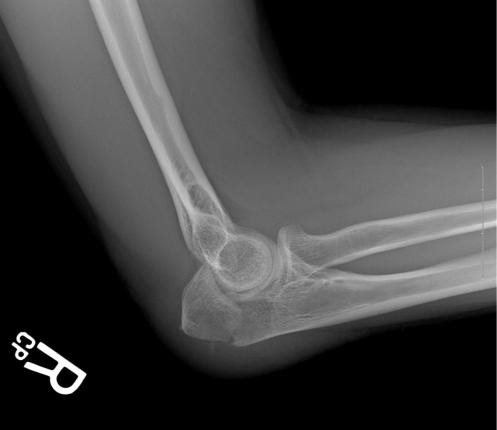

Рентгеновские снимки контрактуры локтевого сустава